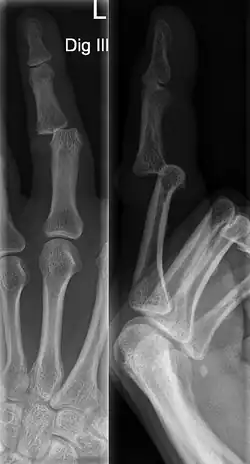

Jammed finger

| Jammed ring finger with minor bruising two days after injury | |

| Symptoms | Swelling, pain, limited range of motion |

| Types | Sprain, dislocation, fracture |

| Causes | Axial loading to the finger |

| Diagnostic method | Physical Examination and X-rays |

| Treatment | Dependent on injury severity |